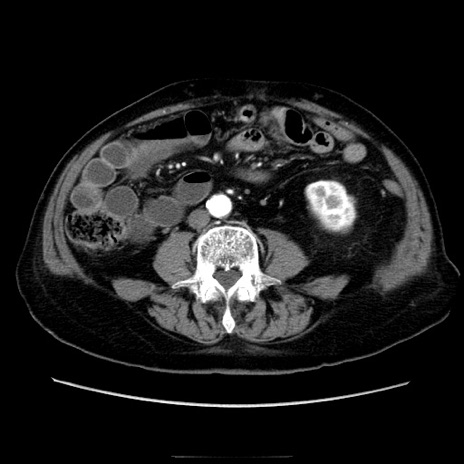

症例21(横断像)

【症例】70歳代男性

【主訴】腹痛

【現病歴】肝硬変・肝細胞癌にてかかりつけの方。約9時間前に食後より腹痛出現。症状が徐々に増悪し、嘔吐出現したため来院。

【既往歴】肝硬変、肝細胞癌(RFA、TACE後)

【身体所見】意識清明、表情苦悶様、BT 36℃、BP 129/78mmHg、P 88bpm、SpO2 97%(RA)、右上腹部から心窩部にかけて圧痛あり、反跳痛なし、筋性防御あり。

【データ】WBC 5800、CRP 0.16